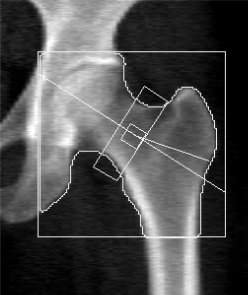

DXA可發出二種不同強度的X光掃描身體,我們選擇正面腰椎掃描、與髖骨包含全髖骨及股骨頸掃描模式,以國際臨床骨密學會規定之擺位與電腦做分析。掃描所需時間約為5-10分鐘。

使用世界衛生組織(WHO)的骨質密度分類標準「T評分(T-score)*」,T負數值越大,表示骨密度越低,骨折風險也越高。(T值≧–1)正常或骨質健康、(–1>T值>–2.5)骨質流失、(–2.5≧T值)骨鬆且值越大骨鬆越嚴重。

健康骨質密度

骨質疏鬆

57歲女性,已停經

身高164cm、體重66kg、BMI 22.63 kg/m2

T值–0.7(正常)

56歲女性,已停經

身高158cm、體重68kg、BMI 27.03 kg/m2

T值–3.4(骨質疏鬆)